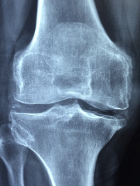

무릎 퇴행성관절염 증상 원인 관리방법 등 무릎 퇴행성관절염 정보에 대해 알아보도록 하겠습니다. 무릎 퇴행성 관절염은 무릎 관절을 보호하는 연골이 점차 손상되고 퇴화되면서 발생하는 만성 질환입니다. 연골이 없어지면 뼈와 뼈가 마찰하게 되어 통증, 염증, 부종, 운동장애 등을 유발합니다. 무릎 퇴행성 관절염은 나이가 들면서 자연스럽게 생기는 것이 아니라, 비만, 과도한 운동, 외상, 유전 등 여러 원인에 의해 발생할 수 있습니다. 무릎 퇴행성 관절염은 치료가 어렵고 재발이 잦은 질환으로, 초기에 적절한 관리를 하지 않으면 점차 악화되어 수술이 필요한 경우도 있습니다.

무릎 퇴행성 관절염은 진단을 위해 X-선 검사, MRI 검사, 혈액 검사 등을 할 수 있습니다. 치료 방법은 증상의 정도와 개인의 상황에 따라 다르지만, 일반적으로 약물 치료, 물리 치료, 운동 요법, 관절 주사, 수술 등이 있습니다.